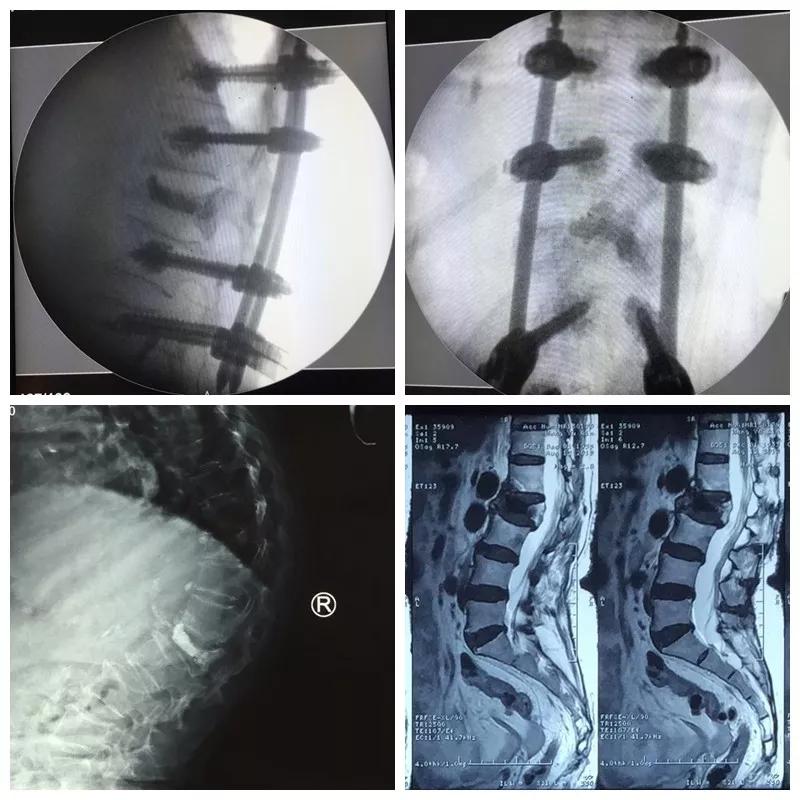

近日,21点玩法研究所 骨一科微创团队为一位85岁高龄的患者,运用骨水泥钉道强化技术治疗腰椎骨折后再发后凸畸形,效果满意。

王奶奶今年85岁,1年前摔倒后因骨质疏松导致了腰2椎体压缩骨折,行介入骨水泥治疗,疼痛解除,效果满意。可是后来王奶奶不小心再一次摔倒,驼背明显加重,并又出现了顽固的腰背疼痛和右下肢抽麻,家人把王奶奶送到21点游戏规则 ,检查后发现,因为严重的骨质疏松,虽然之前骨水泥加强了骨折椎体,但是没有能阻止骨质疏松的加重,再次摔倒又发生了新的骨折,并且骨折块压住了神经,引起下肢抽麻疼痛。骨一科微创团队经过严谨的术前讨计划与准备,给王奶奶实施了微创手术,一次麻醉同时完成了骨水泥钉道强化矫形、神经减压、新发骨折椎体成形术等三个微创手术,术后驼背畸形纠正、下肢抽麻缓解、腰背骨折疼痛解除,效果理想。老人术后驼背改善了、腰背挺直了,再也不用弯着腰低着头走路了,身高也增加了七八公分,老人开心的说道“我觉得自己又年轻了十几岁”。

郭华院长介绍:骨水泥治疗骨质疏松性压缩骨折已成为常规有效的手术,但是对于严重骨质疏松的患者,单纯骨水泥不能够阻止脊柱后凸畸形的发生,传统椎弓根钉棒系统治疗脊柱骨折矫形效果好,但在严重疏松的骨质里没有足够的把持力,而我们采用的骨水泥强化钉道技术把两者优点结合起来,克服了骨质疏松钉子无把持力的技术难题,而且再加入经皮微创置钉技术,可以完美解决老人的后凸畸形问题。